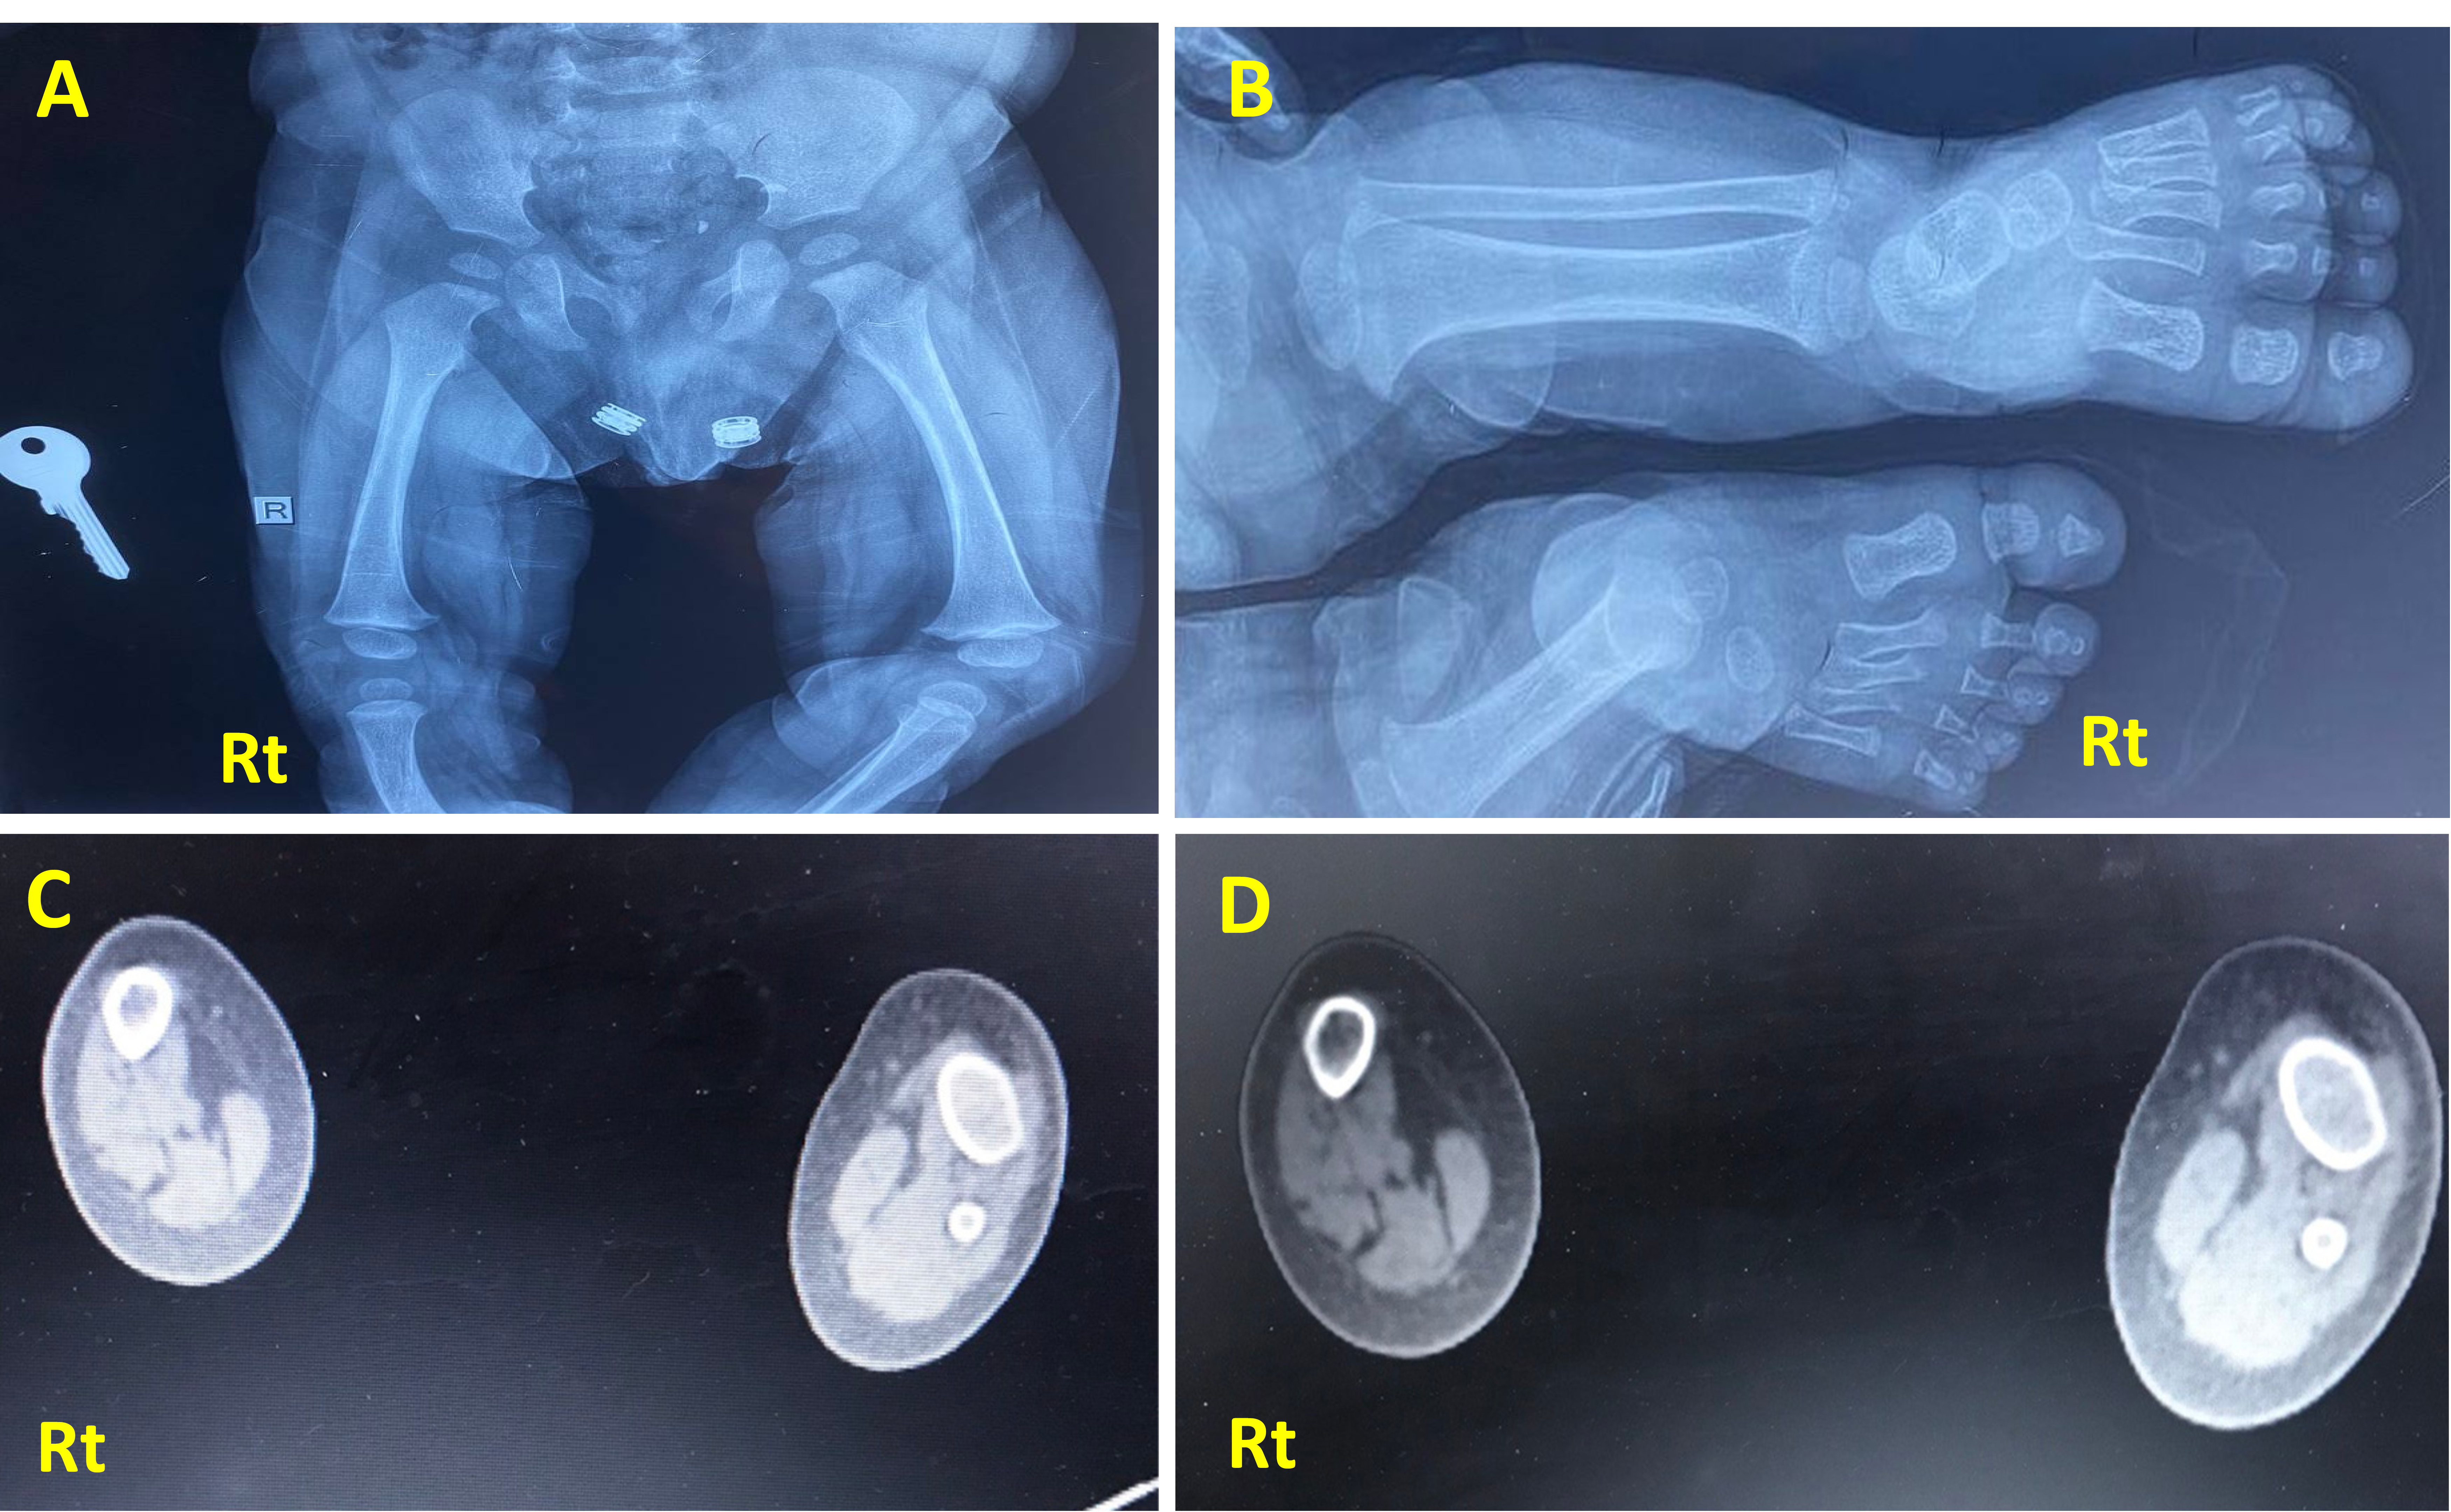

Imaging study, including X-rays (Figs. 2 and 3) and CT scans, confirmed the FH diagnosis and defined its severity. The case involved fibular hemimelia, characterized by fibular hypoplasia, a bowed tibia, and limb shortening, combined with proximal femoral focal deficiency (PFFD), in which the femur is shortened, angulated, or bowed, but demonstrates normal mineralization. PFFD tends to associate with FH in 50% of the cases [13, 14]. The ankle joint, foot, and tibia bone were unaffected. The diagnosis was consistent with type II FH with PFFD.

X-ray of the presented case. (A) Anteroposterior projection of both legs showing a completely absent Rt fibula with limb shortening and limb length discrepancy compared to the Lt side. The tibia is foreshortened, thickened, and bowed with medial rotation. (B) X-ray frontal view of Rt and Lt femur showing underdeveloped Rt femoral head compared to the Lt side, consistent with mild Rt proximal femur deficiency. (C, D): CT scan of both legs (axial section view) showing absent Rt fibula with deficiencies of the related muscular component, with the Rt tibia showing reduced radius compared to the Lt side.

X-ray posteroanterior projection of both Rt and Lt legs; the Rt leg is shortened with thickened bowing of tibial bone, thickened cortex borders, and irregular bony marrow trabeculation compared with the normal Lt leg. Fibula is absent, associated with a hypoplastic, deformed attachment of the distal tibia to the ankle region, and later showing irregular hypoplastic carpal bony fusion.